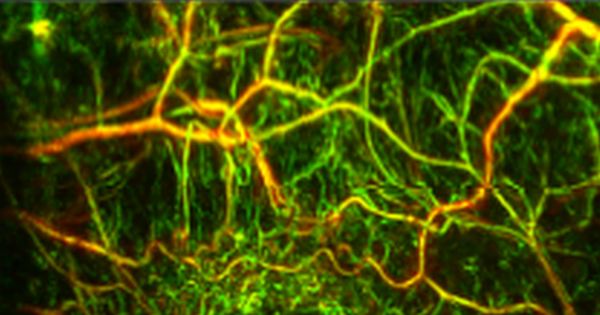

INNODERM intends to develop the RSOM technique into a viable clinical term for assessing vascularization in tumor growth. Credit: INNODERM brochure.